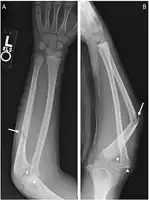

| X-ray of Monteggia fracture of right forearm | |

The Monteggia fracture is a fracture of the proximal third of the ulna with dislocation of the proximal head of the radius. It is named after Giovanni Battista Monteggia.[1][2]

Monteggia fracture dislocation

Monteggia fracture